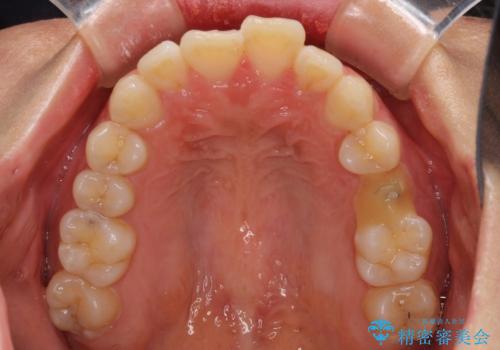

- デコボコの歯列が気になるとことで来院された患者様です。

歯列不正としては軽度であったため、インビザラインでもワイヤー装置でも対応可能でしたが、ご本人の希望によりインビザラインによる矯正治療を行うこととしました。